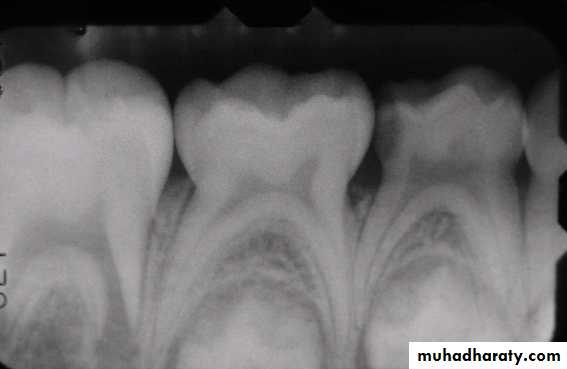

Pulps of Primary Teeth

Relatively larger

Pulp horns are closer to the outer surface

Great variation in size and location

Mesial pulp horn is higher

Pulp chamber shallow

Usually a pulp horn under each cusp